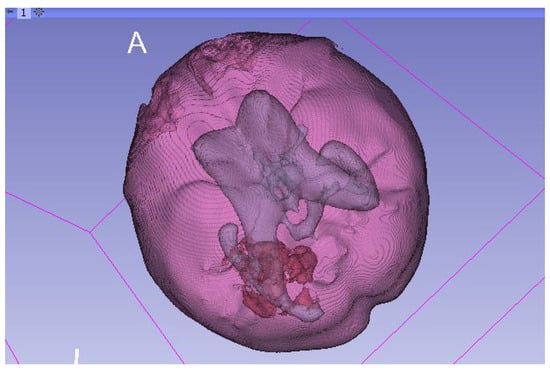

2.4.3. Model Creation and Visualization

2.4.4. Model Correction and Export

2.4.5. Model Refinement and Animation